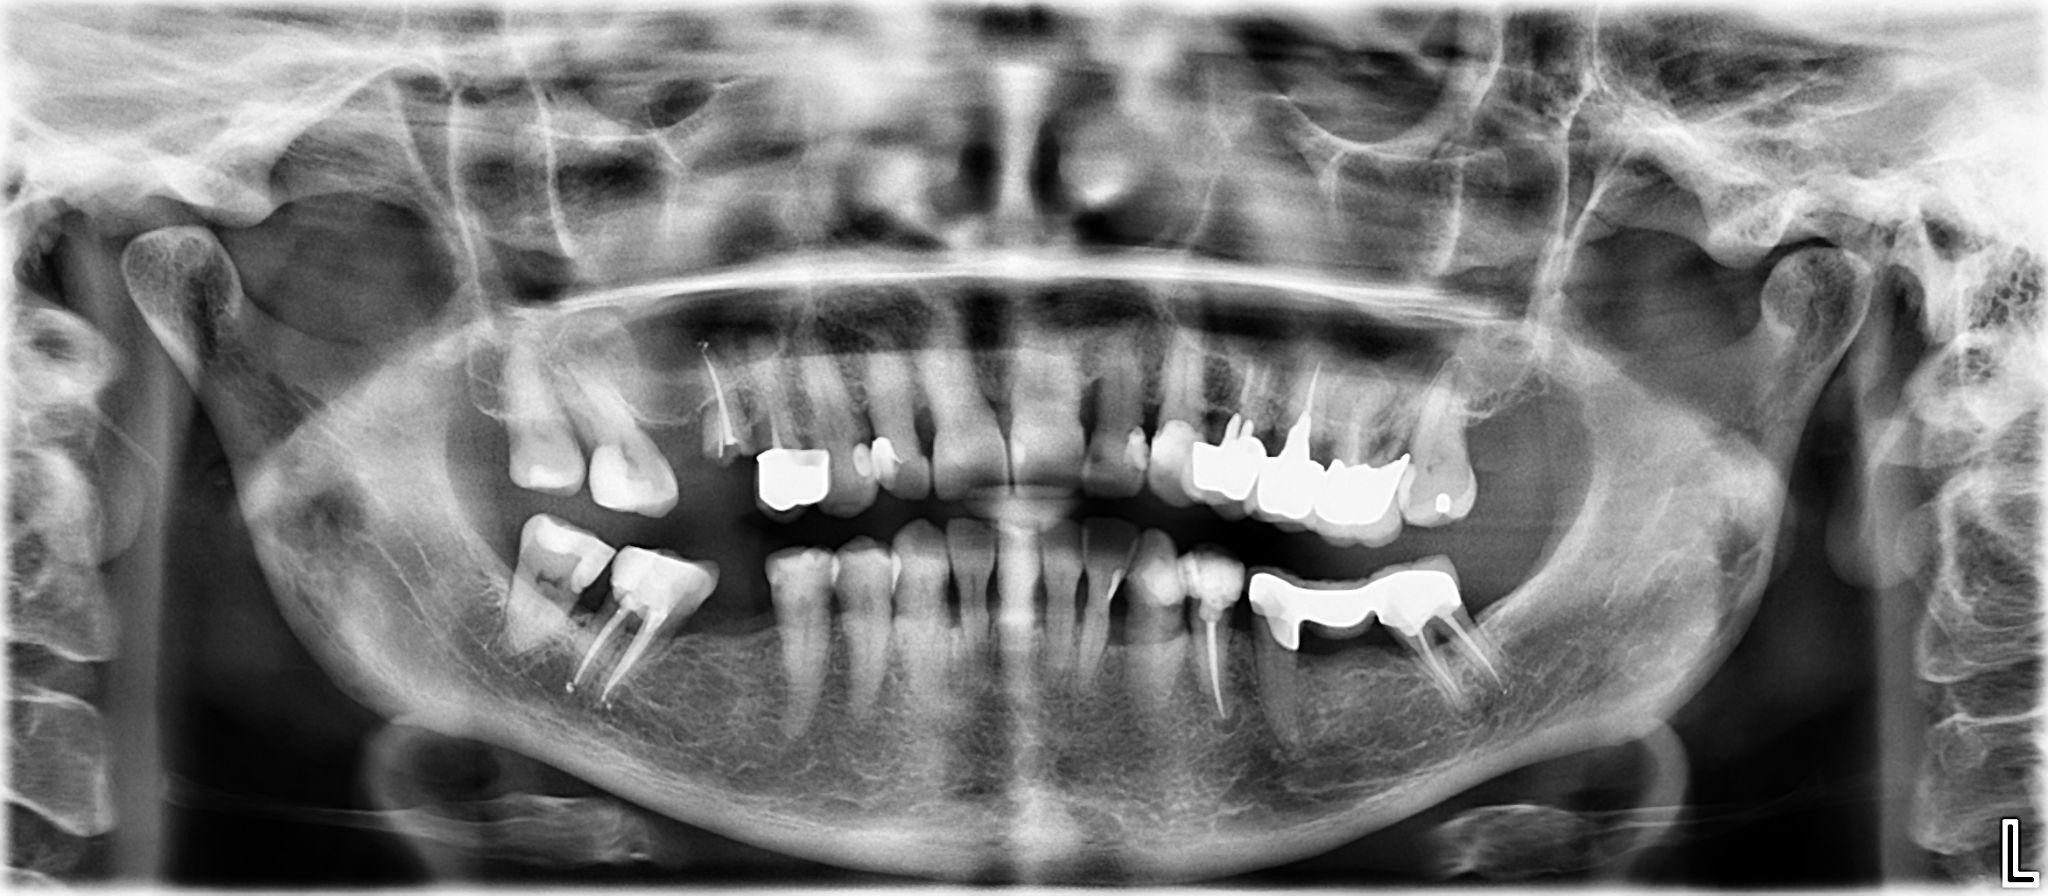

8 / 25

8. What option cannot be selected for the upper jaw of this panoramic X ray?

9 / 25

9. What option cannot be selected for the lower jaw of this panoramic X ray?

10 / 25

10. What option cannot be selected for the first quadrant of this panoramic X ray?

11 / 25

11. What option cannot be selected for the second quadrant of this panoramic X ray?

12 / 25

12. What option cannot be selected for the third quadrant of this panoramic X ray?

13 / 25

13. What option cannot be selected for the forth quadrant of this panoramic X ray?